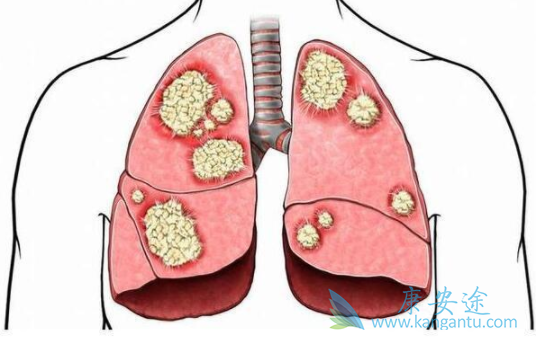

brigatinib(布加替尼)是新一代间变淋巴瘤激酶(ALK)抑制剂,对耐crizotinib治疗的ALK阳性非小细胞肺癌(NSCLC)疗效显著。然而与crizotinib相比,brigatinib在晚期ALK阳性但尚未接受ALK抑制剂治疗的NSCLC患者中疗效尚不清楚。在一个开放标签、3期临床试验,将晚期ALK阳性而以前从未接受ALK抑制剂治疗的NSCLC患者,按照1:1的比例随机分配, 分别接受brigatinib 180mg每天一次或crizotinib 50mg每日两次进行治疗。

第一次中期分析计划在198种预期的疾病进展或死亡事件发生约50%时进行。275位患者被随机分组;137人被分配到brigatinib组,138人被分配到crizotinib组。在第一次中期分析中(发生99种),brigatinib组的中位随访为11.0个月,crizotinib组为9.3个月。brigatinib组的无进展生存率高于crizotinib组(预估12个月无进展生存率67%相比 43%;疾病进展或死亡的危险比为0.49。

275位患者被随机分组;137人被分配到brigatinib组,138人被分配到crizotinib组。在第一次中期分析中(发生99种),brigatinib组的中位随访为11.0个月,crizotinib组为9.3个月。brigatinib组的无进展生存率高于crizotinib组(预估12个月无进展生存率67%相比 43%;疾病进展或死亡的危险比为0.49。